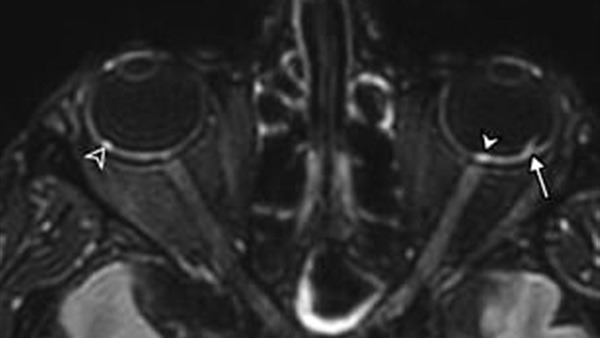

ووفقًا لصحيفة ديلي ميل البريطانية،، فإن الباحثين حذروا من أن الإصابة بفيروس كورونا قد تؤدي إلى التهاب مقل العيون وتؤدي إلى تكوين عقيدات غامضة في الجزء الخلفي من العين.

ولا يعرف الخبراء حتى الآن أسباب هذه العقيدات أو تأثيرها على صحة المريض على المدى الطويل.

ومع ذلك ، كشفت دراسة أجريت على 129 مريضًا فرنسيًا أصيبوا بفيروس Covid-19 خضعوا لفحوصات التصوير بالرنين المغناطيسي أن تسعة منهم ما يساوي (سبعة في المائة) يعانون من تشوهات في العين .